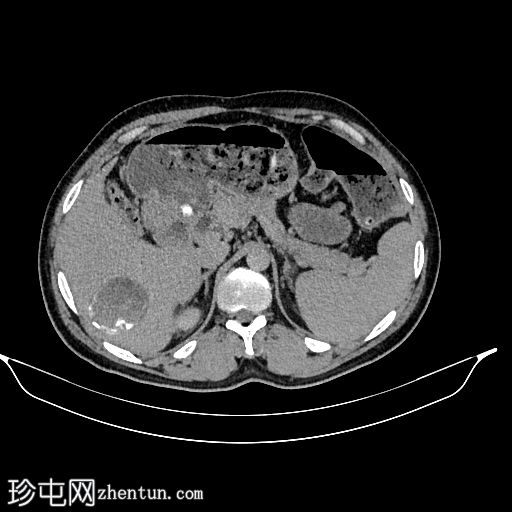

轴位增强扫描(延迟期)

肝脏VII段可见一边界清晰的囊性病变,内部有分隔,囊壁可见钙化。

右肾中央部分(肾门)可见一囊性病变,中心可见基质,周围可见子囊。该病变与肾盂肾盏无交通。病变周围可见两处高密度影,位于上、中肾盏,无法区分是结石还是病变壁钙化。另可见上极肾盏中度扩张。